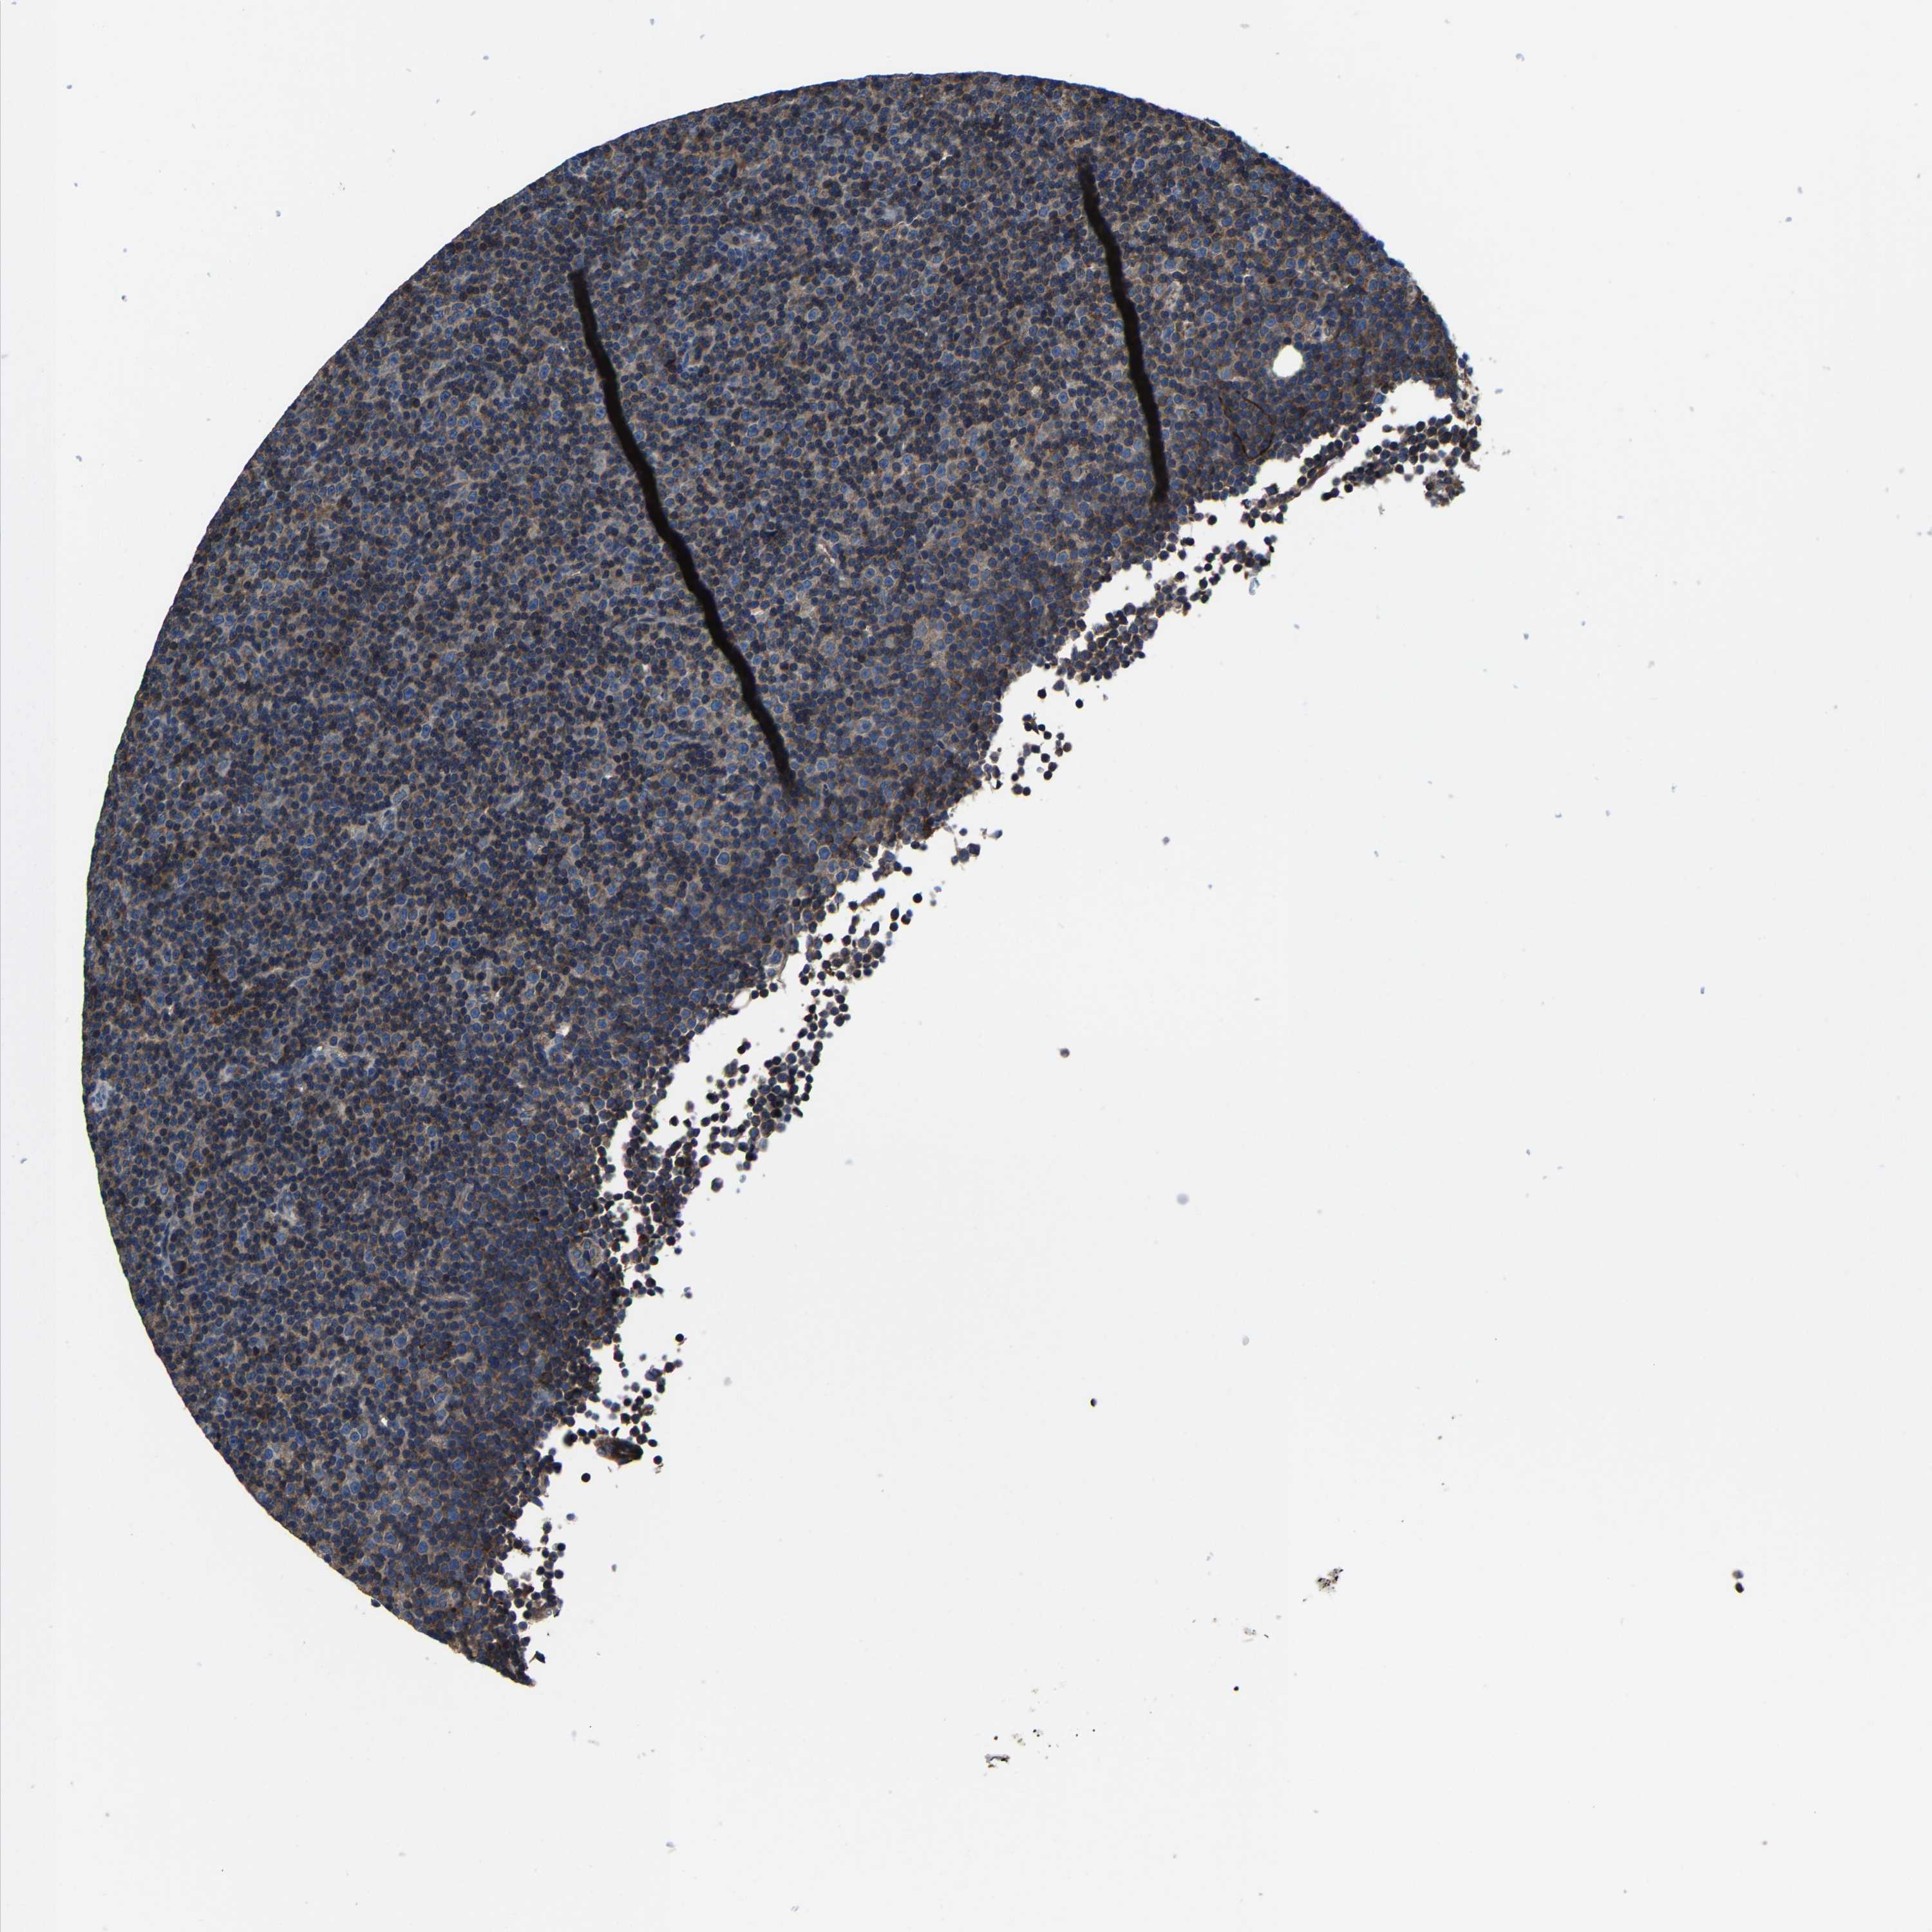

CANCER LYMPHOMA Show tissue menu

LYMPHOMA - Protein expressioni

A mouse-over function shows sample information and annotation data. Click on an image to view it in a full screen mode. Samples can be filtered based on level of antibody staining by selecting one or several of the following categories: high, medium, low and not detected. The assay and annotation is described here.

Each image is clickable and will lead to virtual microscopy that enables deeper exploration of all samples and also displays staining intensity scores, fraction scores and subcellular localization as well as patient and tissue information for each sample.

Antibody HPA020625

Staining

High

Medium

Low

Not detected

Intensity

Strong

Moderate

Weak

Negative

Quantity

>75%

75%-25%

<25%

None

Location

Nuclear

Cytoplasmic/membranous

Cytoplasmic/membranous,nuclear

Hodgkin's disease, NOS

Malignant lymphoma, non-Hodgkin's type, High grade

Malignant lymphoma, non-Hodgkin's type, Low grade